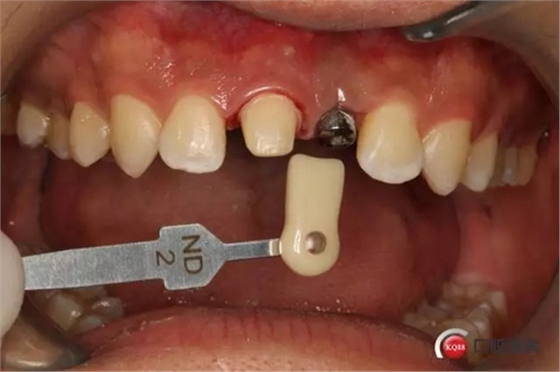

種植后修復(fù),我們要把握每一個(gè)細(xì)節(jié),比色,轉(zhuǎn)移桿的就位,我們必須把臨床做好,技工師傅才會(huì)給我們做出好的修復(fù)體,減少一些不必要的失誤,首先術(shù)前的檢查是必要一步 ,再是器械的準(zhǔn)備使我們臨床操作有條不紊,術(shù)前拍照,o-bite取咬合記錄,消毒修復(fù)術(shù)區(qū),旋出愈合基臺(tái),生理鹽水沖洗袖口,拍照袖口,安放合適轉(zhuǎn)移桿,拍X線見(jiàn)轉(zhuǎn)移桿就為良好,硅橡膠取模,術(shù)后旋回愈合基臺(tái),拍照比色。